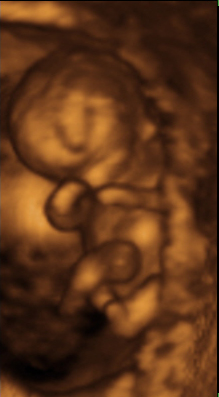

Desarrollo fetal en el segundo mes de embarazo

Hacia la sexta semana aparecen los esbozos de los brazos y piernas. Comienzan a distinguirse los ojos, aunque en situación bastante más lateral a la definitiva. El cuerpo se encuentra plegado sobre sí mismo, de manera que la cara está tocando el tórax y el abdomen.

Entre la séptima y octava semana comienza a distinguirse la nariz en su lugar definitivo así como los procesos auditivos. En la octava semana aparece ya los dedos en manos y pies.

Al final de este segundo mes el embrión ya alcanza los 2 cm y pueden identificarse en él los principales caracteres externos del cuerpo.